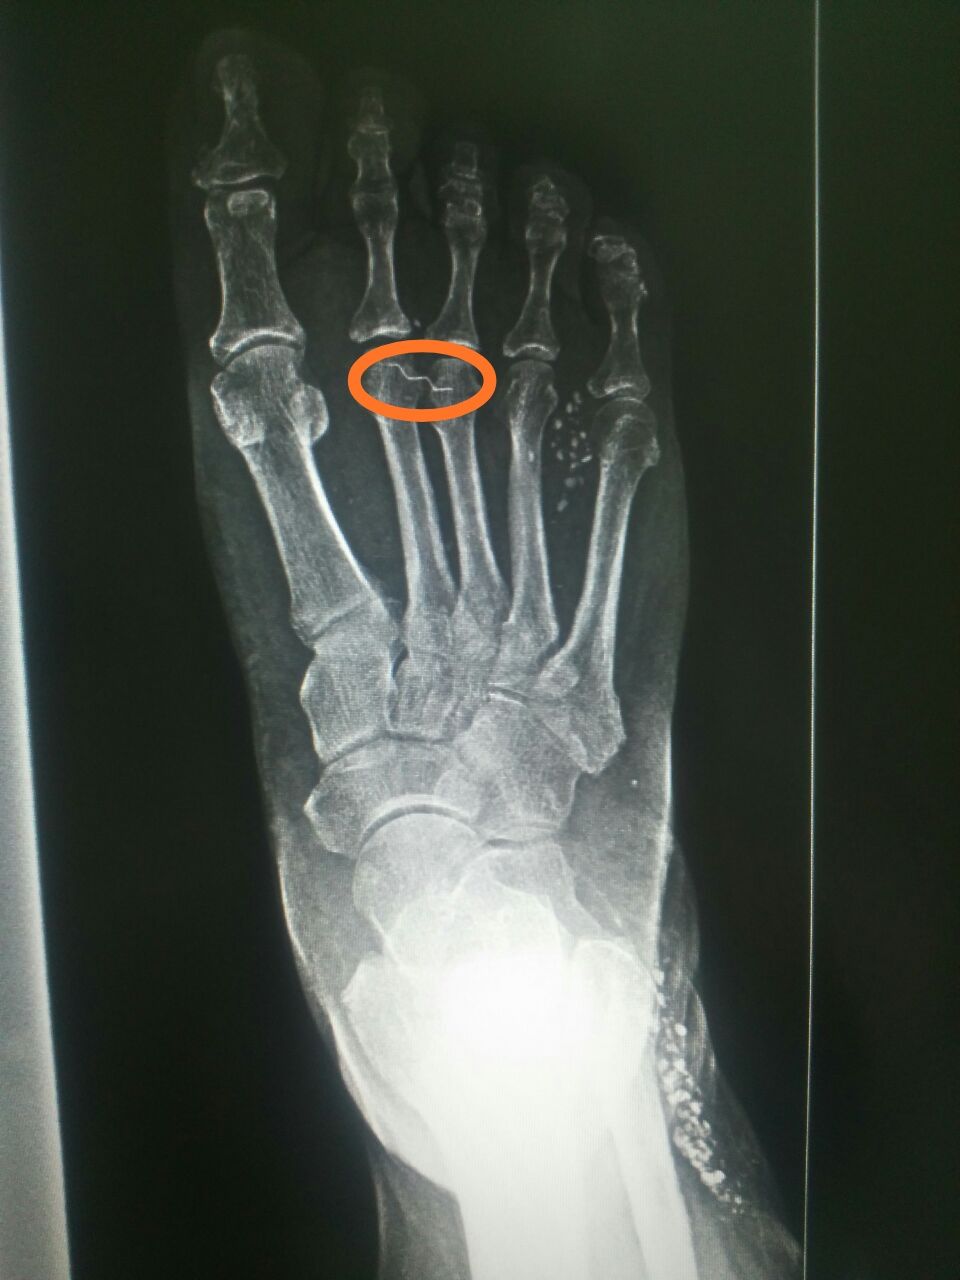

Здравствуйте. Ж 1956 г.р.

Коллеги как оценить кальцификаты

Не похож на кальцификации

Не оскольки?

Дробинки?

Что за проволока...

Это по моему травма... Производственная новерно...

А ещё в области малоберцовой что-то